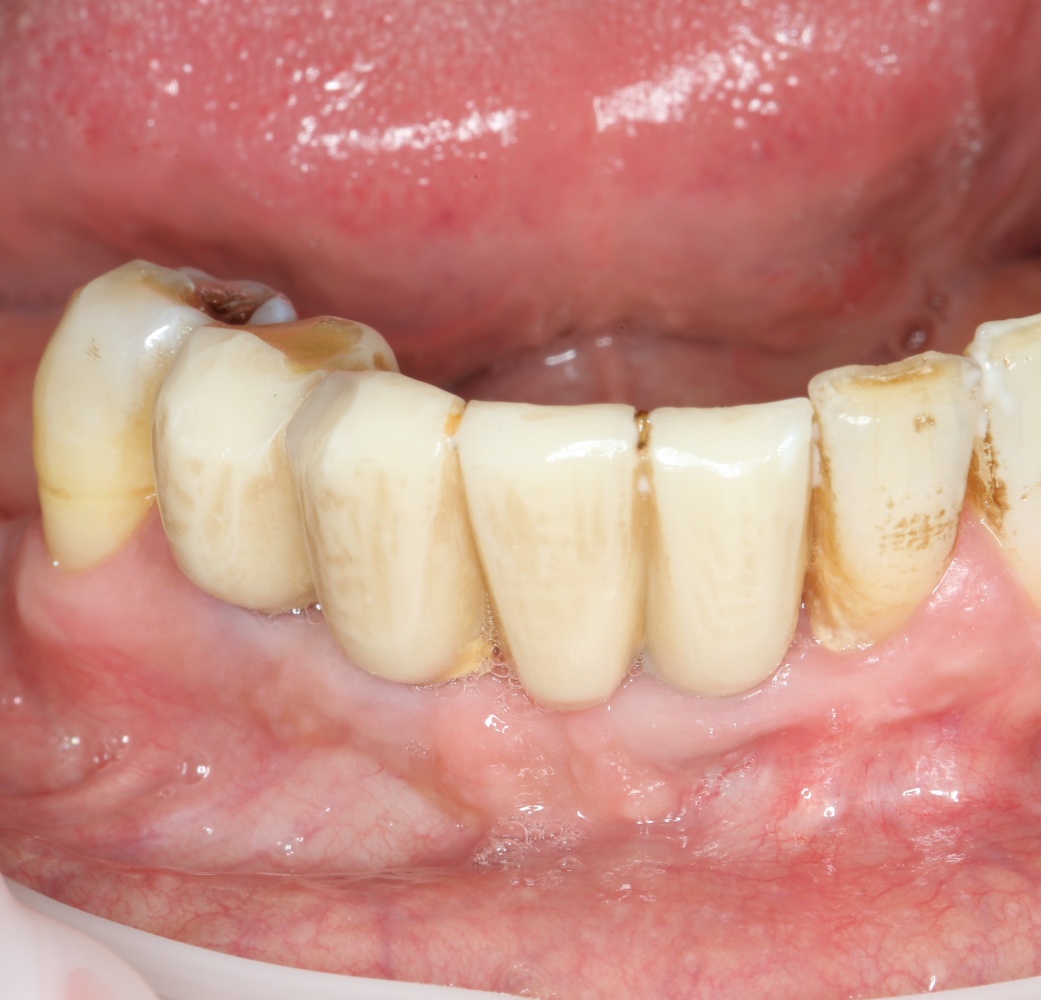

Рекомендации по установке имплантов. Для всех. Часть V.